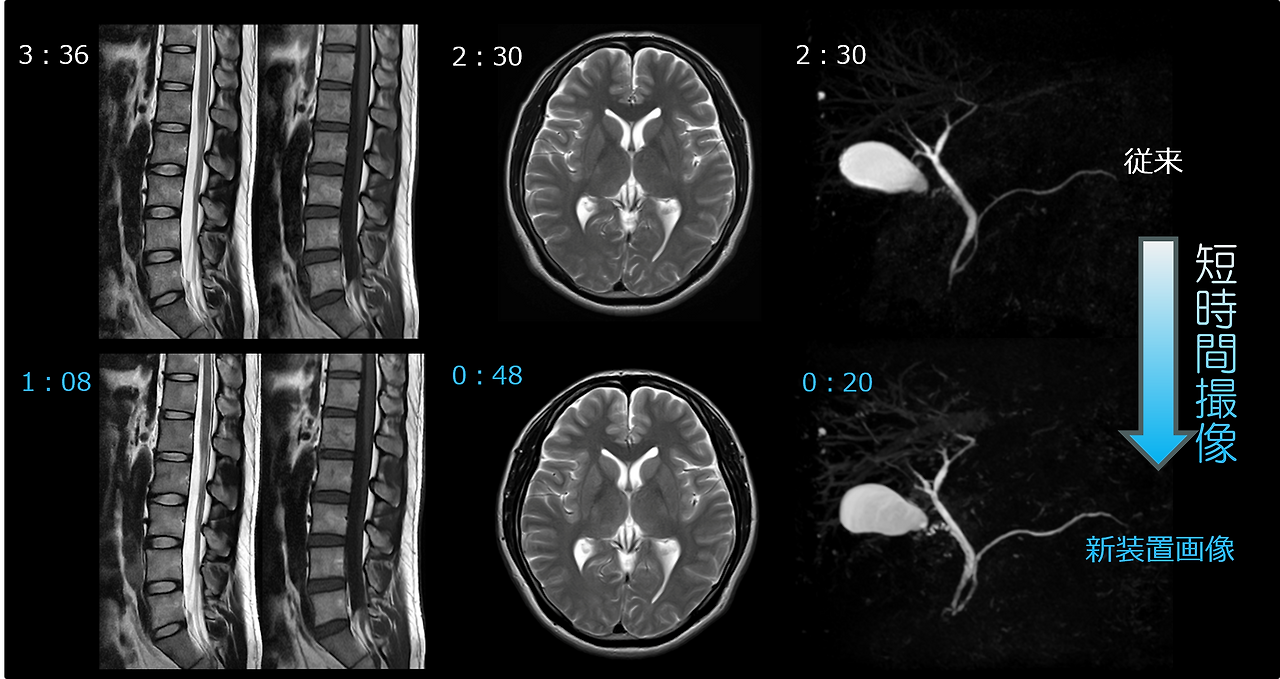

검사 시간은 많은 분들이 생각하는 것보다 조금 더 여유 있게 잡는 편이 좋습니다. 삼성서울병원 안내에 따르면 MRI는 보통 30분에서 60분 정도 검사를 하며, 질환이나 부위에 따라 시간이 늘어날 수 있습니다. 뇌 MRI 단독 촬영은 일반적으로 30분 안팎에서 50분 전후로 안내되는 경우가 많고, 조영제 사용이나 추가 시퀀스가 들어가면 더 길어질 수 있습니다. 여기서 중요한 점은 실제 장비 안에 들어가 있는 순수 촬영시간과 병원 도착부터 귀가까지의 총 소요시간은 다르다는 것입니다. 접수, 문진, 금속물 제거, 환복, 조영제 라인 확보, 대기, 촬영 후 설명까지 포함하면 병원 체류시간은 1시간 30분에서 2시간 이상이 되는 경우도 적지 않습니다. 따라서 직장인이라면 단순히 “MRI는 30분”이라고 생각하지 말고, 최소 반나절 정도 일정 여유를 두는 편이 현실적입니다.

검사 시간이 길어지는 대표적인 경우도 따로 있습니다. 조영제를 사용하는 경우가 가장 대표적이고, 환자가 중간에 움직여 영상이 흔들리면 재촬영이 필요해 시간이 늘어날 수 있습니다. 또한 폐쇄공포감이 심해 검사 도중 중단하거나, 어린이처럼 협조가 어려운 경우에는 일반 성인보다 더 긴 준비가 필요할 수 있습니다. 반대로 비교적 단순한 비조영 뇌 MRI는 예약 시간에 맞춰 원활히 진행되면 생각보다 빠르게 끝나는 편입니다. 실제로 환자가 체감하는 피로감은 검사 자체 시간보다도 “가만히 있어야 하는 시간”과 “장비 소음”에서 오는 경우가 많기 때문에, 편한 복장으로 가고, 긴장 완화를 위해 검사 전 설명을 충분히 듣는 것이 도움이 됩니다.